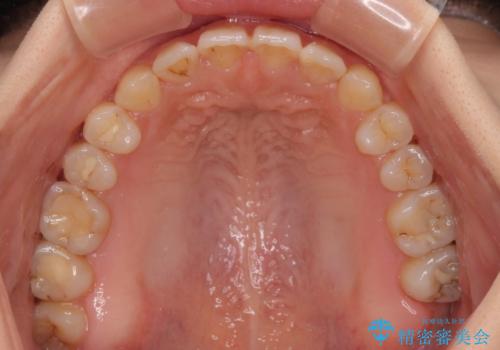

オープンバイトは舌の突出癖により誘発され、治療後も突出癖が残っている容易に後戻りしてしまいます。

治療期間を短縮するためにも、舌突出癖の改善が極めて重要となります。

特にインビザラインではIPRという歯と歯の間を削る処置を多用するため、後戻りによりスペースが生じやすくなるため、治療初期段階での舌のトレーニングが必須となります。